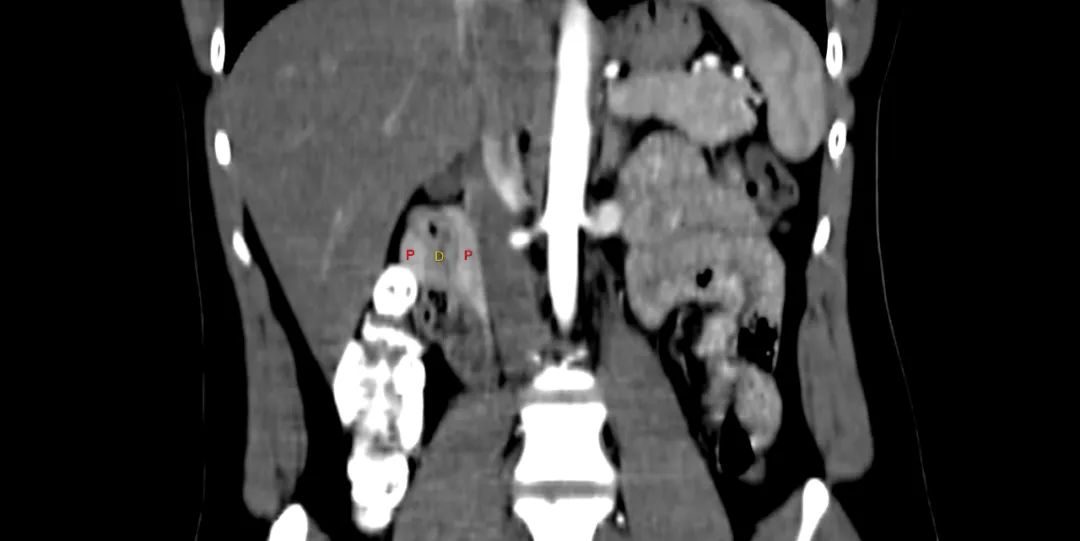

带注释的动脉期图像显示增强胰腺实质(标记为P)完全包裹十二指肠(标记为D)。

环状胰腺是由腹芽不旋转导致十二指肠被胰腺不同程度包裹的结果。完全性环状胰腺出现在新生儿有梗阻,并可偶然发现在成人,胰腺炎可能是成人的一种表现特征。